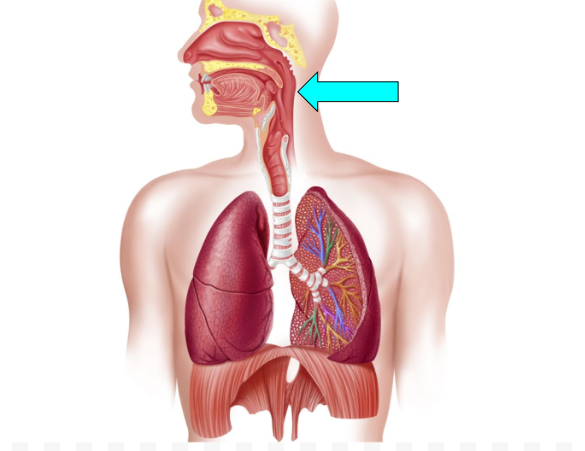

Pharynx (pic)

Pharynx

passageway for air & food